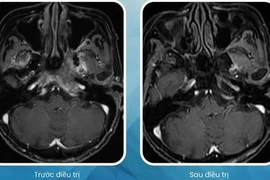

Các nhà khoa học Trung Quốc đã phát triển một phương pháp điều trị mới cho các bệnh ung thư vòm họng. Đó là phác đồ điều trị miễn dịch mới kết hợp hóa xạ trị.